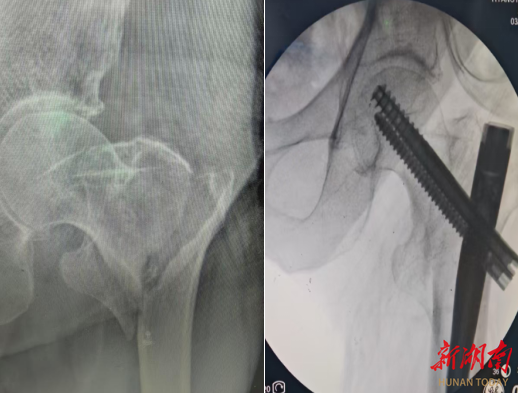

术前术后对比图。

手术过程十分顺利,麻醉医生为老人实施椎管内麻醉,保障术中无痛安全。副院长胡胜云带领手术团队借助仪器精准复位骨折部位,仅在老人左髋外侧开3个微小切口,最大仅3厘米、最小仅1厘米,便完成了骨折固定操作。整场手术仅耗时1小时,出血量仅约100毫升,高效又安全的手术,为老人的康复打下了坚实基础。